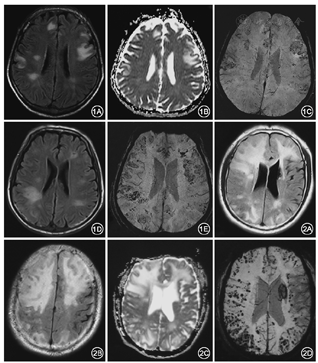

所有患者颅脑MRI均显示T2WI和Flair序列不对称的皮质下白质高信号,ADC值增高,符合血管源性水肿(图1,图2)。各脑叶均受累及,以额顶叶受累最重,枕叶最轻。5例患者伴有明显占位效应。增强扫描1例患者病灶呈轻度结节样强化,1例伴软脑膜强化。2例发现多发皮质或皮质下急性微小梗死灶。SWI均显示皮质及皮质下多发微出血灶(图1,图2)。2例患者同时行GRE T2*序列,显示微出血病灶数目明显少于SWI。6例患者MRA均未见明显血管狭窄。

经患者及家属知情同意后4例患者接受了免疫抑制治疗。1例患者甲泼尼龙500 mg冲击治疗5 d后症状改善,出院口服泼尼松1 mg/kg缓慢减量并每周静脉应用环磷酰胺800 mg至总量15 g,1个月后复查腰穿脑脊液压力及蛋白定量降至正常,随访1年症状无复发。2例患者单用甲泼尼龙冲击治疗后症状改善,复查MRI病灶明显减少,改泼尼松口服减量过程中复发,复发后颅脑MRI见新发病灶(图1),SWI示微出血增多(图1),病情逐渐加重死亡。1例患者静脉应用地塞米松10 mg后症状略改善,出院后失访。所有应用激素患者治疗期间监测血压血糖,同时应用胃黏膜保护剂、钙剂等预防相关不良反应;应用环磷酰胺患者定期监测血常规、尿常规、肝肾功等,治疗期间未出现明显药物相关不良反应。